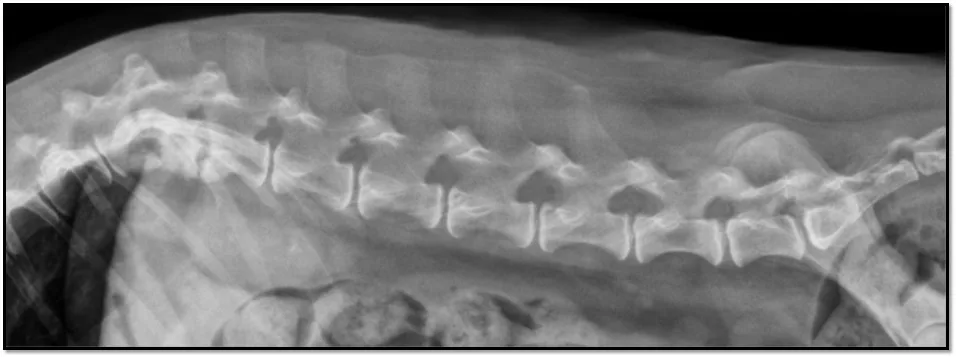

Plain lateral thoracolumbar spinal radiography was performed to pursue an etiology for the spinal pain.

FIGURE Lateral radiograph

The T12-T13 (black arrow) and T13-L1 (white arrow) vertebral end plates were sclerotic and irregular with areas of lysis, and the T12-T13 intervertebral disk space appeared collapsed with possible subluxation of the articular processes. A second view would be needed to evaluate lateral subluxation.

Radiographs were suggestive of discospondylitis. Discospondylitis is most commonly diagnosed in young, large-breed hunting dogs but should be considered in any patient with acute, focal spinal pain with or without myelopathy. Bacterial and fungal organisms can cause discospondylitis. Staphylococcus spp, Streptococcus spp, and Pasteurella spp are commonly reported bacterial etiologies; Aspergillus spp is the most commonly reported fungal etiology in dogs. Cultures of urine, blood, or disk material may aid in diagnosing the causative agent.